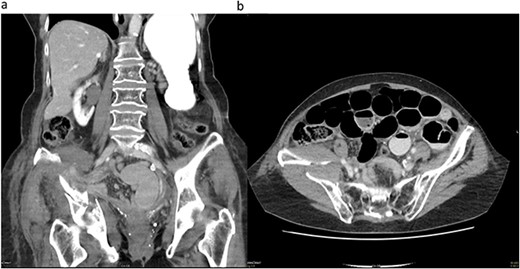

During laparoscopy, distended small bowel loops, predominantly in the right lower abdomen accompanied by bloodstained ascites in all four quadrants, were present. An incomplete herniated loop was identified between the fractured fragments of the lamina quadrilateralis of the acetabulum on the right side. The myopectineal orifice was intact, without femoral or inguinal hernias. The herniated loop was freed from the defect, which measured about 20 × 5 mm. Minor oozing from the fracture was noted during the procedure. To create a tamponade and to avoid another herniation, we patched the hernia orifice with mesenterial fat from the ileocecal region with three resorbable intracorporal stitches (Fig. 2).

(a) Herniated loop (arrow) between the fractured fragment and (b) mesenterial fat patch.